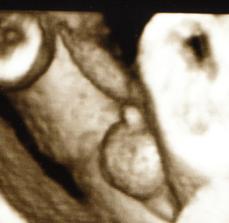

Začali sme sa nanovo snažiť tak uvidíme ako dlho to potrvá dostať sa k cielu.15.12.2009 som dostala taký predčasný vianočný darček // na testíku. 18.12 boli sme u dr ešte nebolo nič vidieť tak maminu pochytila panika ale hcg je 465 takže tehu sme len ešte malíčko a zase sa bojím či je to ok:-// 23 sme boli u dr chytili ma ladviny tak som dostala ant. ale fazulka sa má zatial ok je presne tak kde má byť vačok má 8 mm a už je tam aj základ bábenka.🙂)) Aby ani druhé bábenko nezaostávalo za Kubkom tak mamine je zase poriadne zle už aby bol 12 tt a trochu to prešlo. 14.1 boli sme kontrole všetko ok krásne bilo srdiečko. Dostali sme tehu knižku a prenatal box. 28.1 nás čaká ultrazvuk tak sa už moc teším.Stále my je dosť špatne a už aj vraciam čo už:-/// 2.2. dnes sme boli na utz všetkoje v poriadku aj ked dr najskôr bábo nemohol nájsť po chvílke ho predsa vypátral. všetko je ok bábenko meria 6,68 cm a crl má 4,6 cm. tak na dalšej kontrole sme sa dozvedeli že naše prekvapenie bude chlapček tak budeme mať Mateja- Maťka dalšia poradna za namy všetko ok dalšia nás čaká 7 apríla a konečne znova uvidíme drobčeka. Všetko dopadlo dobre Matejko je trošku večší ale hlavne je ok. 10.5 Gtt hádam budu dobré výsledky inak všetko v norme len bruško je trošku večšie o 2 týždne kontrola tak uvidíme na tvrdnutie sme dostali mange b6 2x dene tak hádam to pomože. Boli sme na sone 17.6 a Matko chce asi predbehnut porodnou váhou Kubka už teraz má 2107 g a aj ostatné rozmery su chválihodné inak je všetko v poriadku pekne si kopká a už sa moc tešíme